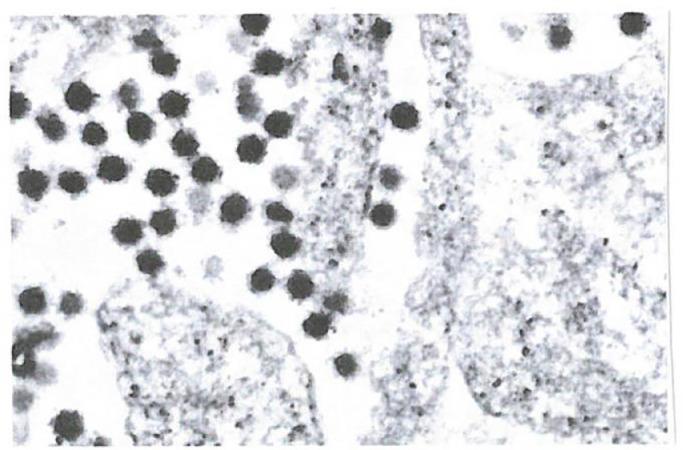

The local antiviral photodynamic inactivation (PDI) may prove to be a helpful tool reducing the viral load in the nose and throat area in the early phase of a Covid19 infection. Both the infectivity and the prognosis of SARS-CoV-2 infections in the early phase can depend on the viral load in this area. The aim of our study was to find a simplified PDI therapy option against corona viruses in this region with low dose methylene blue (MB) as photosensitizer and use of LED light instead of laser. As a substitute for SARS-CoV2 viruses we started with BCoV infected U373 cells first. We used an 810nm diode laser with 300mW/cm2 and 100J/cm light dose as well as a 590 nm LED and a broadband LED with irradiation intensity of 10,000 lx each (irradiation time 2.5 and 10 min) and concentrations of the sensitizer of 0.001% and 0.0001%. The 0.001% MB sensitizer experiments showed similar results with all exposures. The logarithmic reduction factor varied between ≥ 5.29 and ≥ 5.31, (0.001% MB sensitizer) and ≥ 4.6 and ≥ 5.31 (0.0001% MB) respectively. Extending the LED irradiation time from 2 to 5 and 10 minutes did not change these results. In contrast approaches of BCoV-infected cells in the dark, treated with 0.001% and 0.0001% MB sensitizer alone, a lot of residual viruses could be detected after 10 minutes of incubation (RF 0.9 and RF 1.23 for 0.001% MB and 0.0001% MB respectively) In our SARS-CoV-2 experiments with VERO E6 infected cells the irradiation time was reduced to 1, 2 and 3 minutes for both concentrations with increasing broadband LED radiation intensity from 20 to 50 and 100.000 lx. (RF 4.67 for 0.001% and 0.0001% respectively). This showed a minimum concentration of 0.0001%MB and a minimum radiation intensity of 20,000 lx leads to a 99.99% reduction of intracellular and extracellular viruses after one minute exposure.

局部抗病毒光动力灭活(PDI)可能被证明是一种有用的工具,可以降低新冠病毒感染早期鼻腔和喉咙区域的病毒载量。SARS-CoV-2 感染的传染性和预后在早期都可能取决于该区域的病毒载量。我们的研究目的是找到一种针对该区域冠状病毒的简化 PDI 治疗方案,使用低剂量亚甲蓝(MB)作为光敏剂,并使用 LED 光代替激光。作为 SARS-CoV2 病毒的替代品,我们首先使用感染了 BCoV 的 U373 细胞进行了研究。我们使用了 810nm 二极管激光,光密度为 300mW/cm2 和 100J/cm,以及 590nm LED 和宽带 LED,每个 LED 的辐照度为 10,000 lx(辐照时间分别为 2.5 和 10 分钟),敏化剂浓度分别为 0.001%和 0.0001%。在所有暴露条件下,0.001%MB 敏化剂实验均显示出相似的结果。对数减少因子分别为≥5.29 和≥5.31(0.001%MB 敏化剂)和≥4.6 和≥5.31(0.0001%MB)。将 LED 辐照时间从 2 分钟延长至 5 分钟和 10 分钟,并没有改变这些结果。相比之下,对于在黑暗中用 0.001%和 0.0001%MB 敏化剂单独处理的 BCoV 感染细胞,孵育 10 分钟后仍能检测到大量残留病毒(RF 0.9 和 RF 1.23,分别用于 0.001%MB 和 0.0001%MB)。在我们用感染了 SARS-CoV-2 的 VERO E6 细胞进行的实验中,将辐照时间缩短至 1、2 和 3 分钟,两种浓度的宽带 LED 辐射强度分别从 20 增加到 50 和 100.000 lx。(分别为 0.001%和 0.0001%的 RF 4.67)。这表明,最低浓度为 0.0001%MB,最低辐射强度为 20,000 lx,在一分钟的暴露后,可将细胞内和细胞外病毒减少 99.99%。